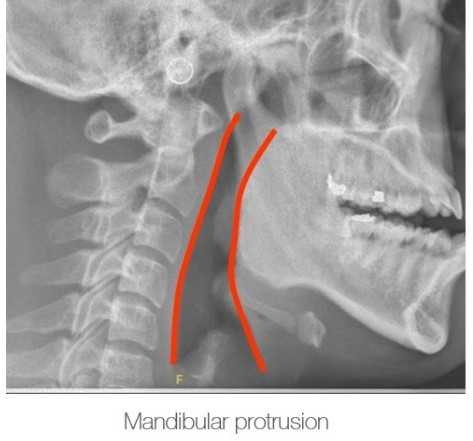

將下顎向前延伸至最大距離 Protrude the mandible to its maximum extent.